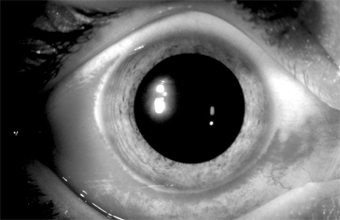

Figure 5-1

Figure 5-1: Gonococcal conjunctivitis. Profuse purulent exudate. (Courtesy of L Schwab.)